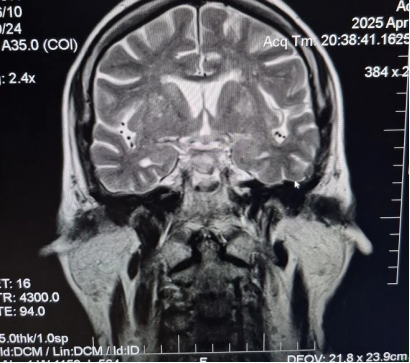

Затем, 17.12.2022, прошла МРТ головного мозга (рис. 4, рис. 5, рис. 6).

Рис. 4. МРТ головного мозга (T1 SE sag)

Рис. 5. МРТ головного мозга (T2 TSE)

Рис. 6. Заключение МРТ головного мозга от 17.12.2022